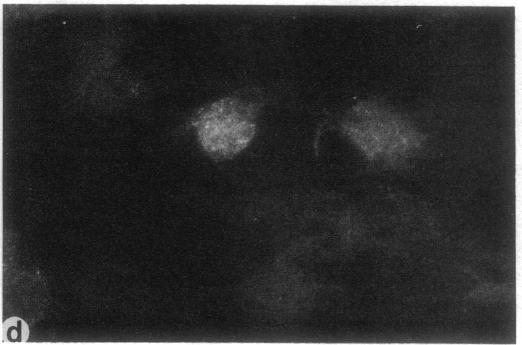

Cells from patients with peroxisome-deficient disorders contain membrane ghosts devoid of most matrix contents instead of normal peroxisomes indicating that the underlying molecular defects impair the import of matrix proteins into these peroxisome ghosts. Genetic heterogeneity for the molecular defects was inferred from the assignment of patients with peroxisome-deficient disorders into nine complementation groups. The aim of our studies was to analyze cell lines from six different complementation groups in a systematic manner for the presence of peroxisome ghosts, the ability to import Ser-Lys-Leu-containing proteins into peroxisome ghosts and for the presence of cytosolic factors required for peroxisomal protein import. We show that each of the cell lines analyzed contains peroxisome ghosts, but is unable to import matrix proteins as judged by a peroxisomal import assay using permeabilized cells. The addition of wild type cytosol did not restore the capacity to import matrix proteins but cytosol prepared from these cell lines was functional in stimulation of peroxisomal protein import in a heterologous system. These results implicate organelle-associated molecular defects in each of the six cell lines analyzed.

过氧化物酶体缺陷症患者的细胞含有缺乏大多数基质成分的膜空壳,而非正常的过氧化物酶体,这表明潜在的分子缺陷会损害基质蛋白导入这些过氧化物酶体空壳。根据过氧化物酶体缺陷症患者被分为九个互补组,推断出分子缺陷存在遗传异质性。我们研究的目的是系统分析来自六个不同互补组的细胞系,以检测过氧化物酶体空壳的存在、将含丝氨酸-赖氨酸-亮氨酸的蛋白质导入过氧化物酶体空壳的能力以及过氧化物酶体蛋白导入所需的胞质因子的存在情况。我们发现,所分析的每个细胞系都含有过氧化物酶体空壳,但通过使用通透细胞的过氧化物酶体导入试验判断,其无法导入基质蛋白。添加野生型胞质溶胶并不能恢复导入基质蛋白的能力,但从这些细胞系制备的胞质溶胶在异源系统中对刺激过氧化物酶体蛋白导入具有功能。这些结果表明,在所分析的六个细胞系中均存在与细胞器相关的分子缺陷。